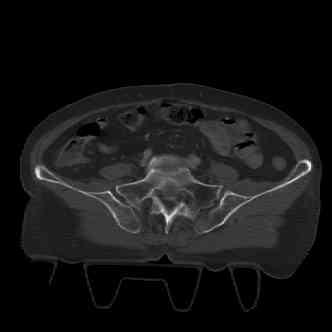

attached are images of a 70 year old female after peds versus car. her own car ran her over.

injuries are limited to the pelvis. left rami open and visible in a 10cm vertical laceration just lateral to left labia majora. wound is grossly clean. no vaginal and no urinary issues. CT scan shows widening of both SI joints anteriorly but I think this is vertically stable pattern.

pt treated that night with I/D and supra-acetabular frame to close the ring. consideration was given for SI screws bilateraly, but given time of night and other factors decision made not to proceed.

so the question is what next operatively if anything? concerns are infection, nonunion anteriorly and possible incompetence of the pelvic floor which may lead to prolapse issues. right rami are comminuted and plating may entail ilioinguinal approach to extend plate laterally to right iliac wing. retrograde screw up right rami is an option but I am not convinced it will add much. adding SI screws very doable, but major concern is restoring anterior ring. so far wound is clean and closed over a drain, and I have no plans to open it back up and wash again.

attached are several CT cuts. please let me know if you need more. the CT is pre-pelvic ex-fix placement.

Thank you.